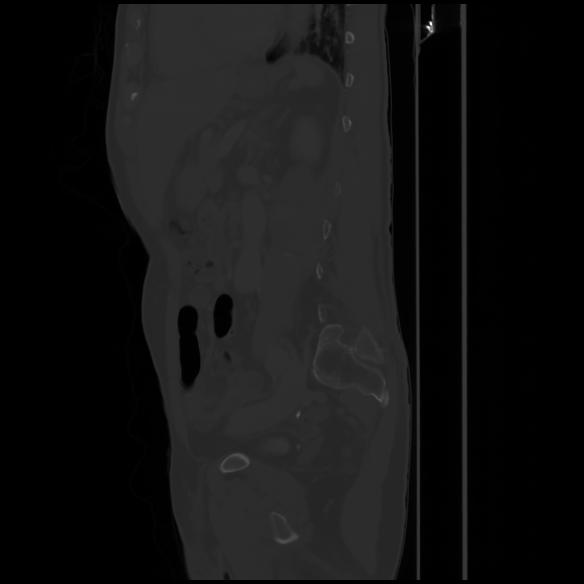

7 CUERPO,CE,Sagittal,3.000,CUERPO,Sagittal,